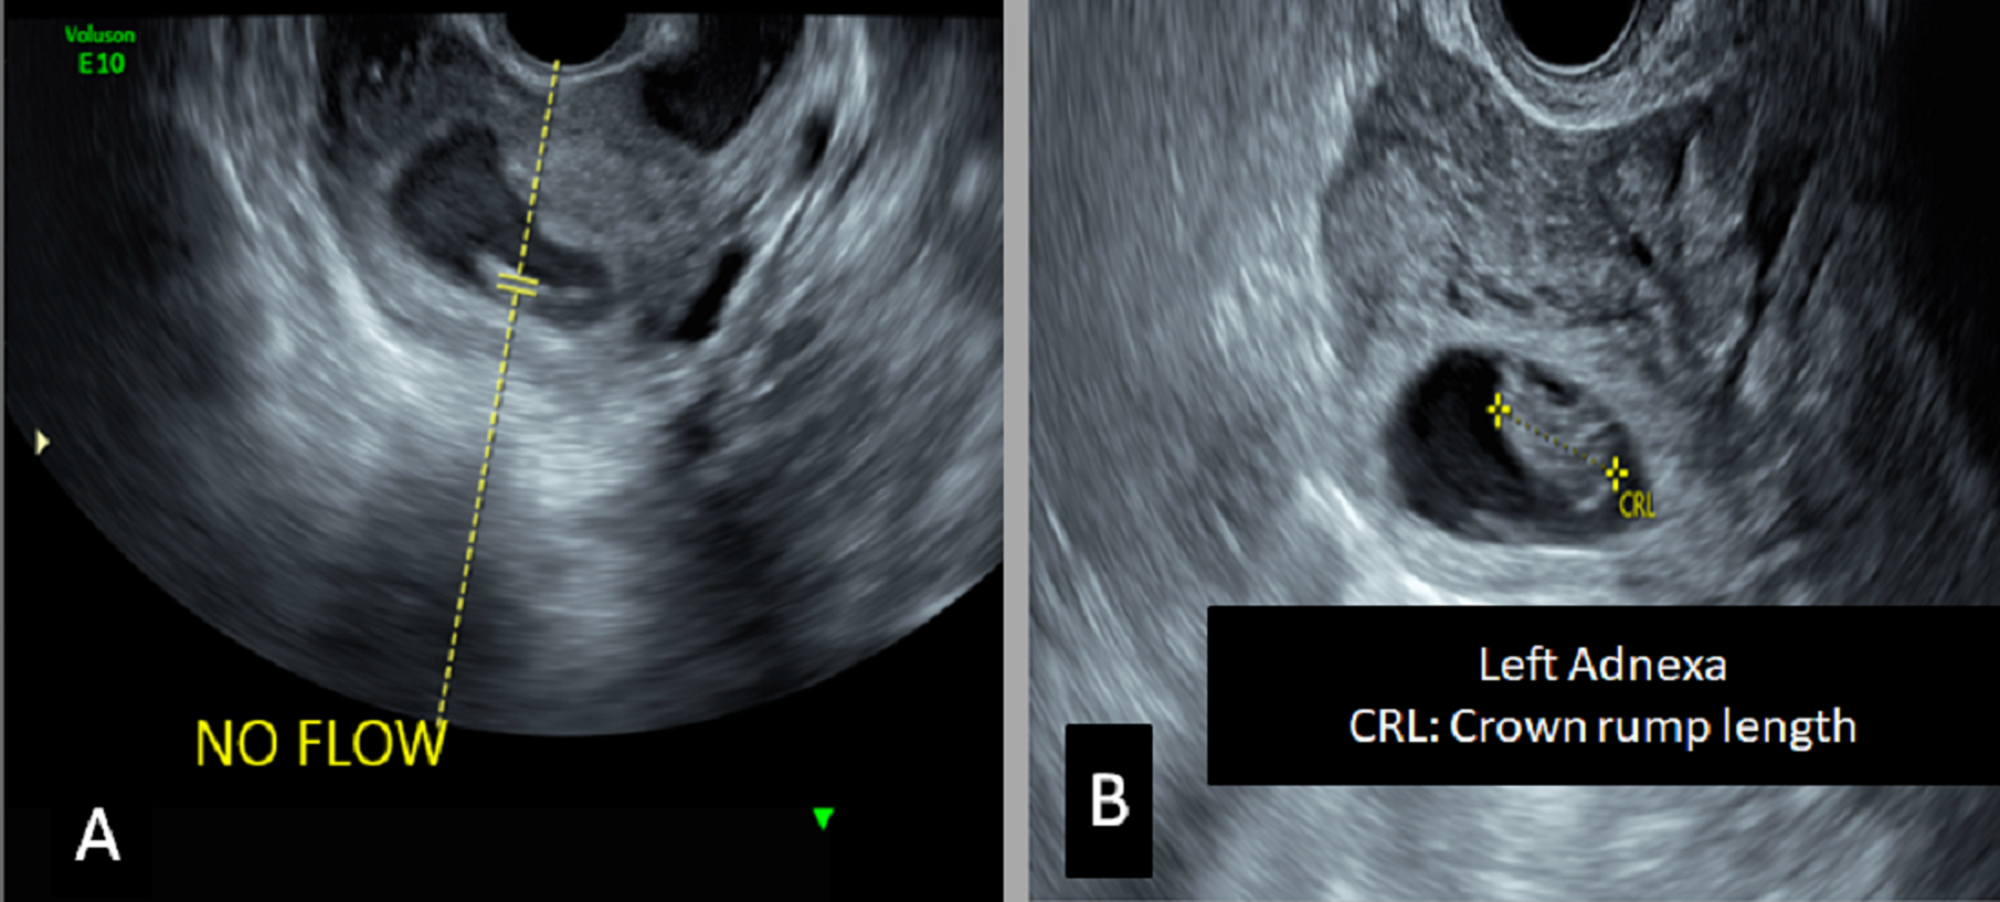

Abstract for heterotopic pregnancy. Heterotopic pregnancy is defined as the coexistence of intrauterine and extrauterine gestation. The course of pregnancy after the surgery was without complications and a healthy baby was delivered at the 39th week of gestation. Heterotopic pregnancy occurs when a patient has simultaneous intrauterine and ectopic pregnancies. The incidence of heterotopic pregnancy is very low.

Hg is commonly identificated when rupture or hemoperitoneum occurs. The diagnosis of hp is still one of the biggest challenges in modern gynecology. Abstract heterotopic pregnancy is the coexistence of living or dead intrauterine pregnancy single or multiple and extrauterine pregnancy located in the oviduct ovary uterine corner cervix or peritoneal cavity. Introduction heterotopic pregnancy hp is defined as the presence of an intrauterine pregnancy iup that coexists with an ectopic pregnancy ep1.

Rates of heterotopic pregnancy have been rising with increased availability and access to in vitro fertilization and other advanced fertility technologies. Hp can occur in several forms eg. When treated properly and on time a heterotopic pregnancy can result in live childbirth with favorable outcomes for both the child and the mother. Symptoms of heterotopic pregnancy are nonspecific such as vague abdominal pain so transvaginal ultrasound is a crucial part of the.